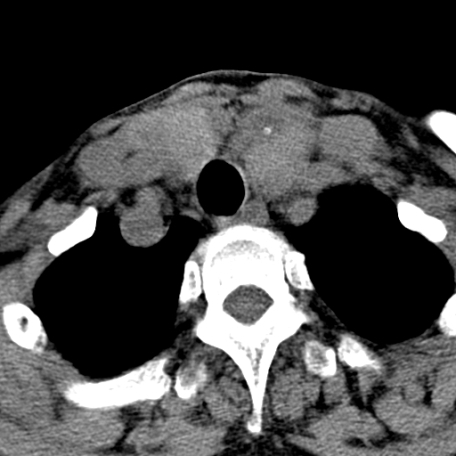

标题: CT24010:患者女56岁双侧甲状腺摘除术后一月复查,患者现感 [打印本页]

标题: CT24010:患者女56岁双侧甲状腺摘除术后一月复查,患者现感

甲状腺术后复发,现在甲状腺区域仍有密度不均匀之软组织密度影。

甲状腺区域密度不均匀密度影,应该是术后改变,要鉴别是否复发,建议增强检查。

“甲状腺摘除术后一月复查”,有病理吗?考虑术后复发,可能是恶性,颌下及左侧颈部淋巴结有肿大。

双侧甲状腺肿大,伴多发低密度灶(性质待定);建议行进一步检查。

双侧甲状腺肿大,周围结构不清,术后复发时间有点短,考虑出血并感染。